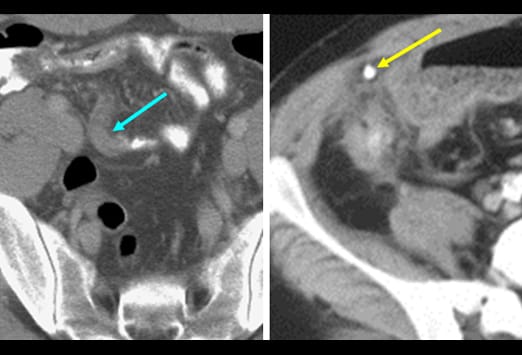

Die Abbildung auf der linken Seite zeigt eine einfache Appendizitis. Hier ist eine Verbreiterung und ein Ödem der Appendix zu sehen, mit einer erhöhten Kontrastmittelaufnahme der Appendixwand (blauer Pfeil) und einer geringen umgebenden Entzündungsreaktion. Beim Fortschreiten einer Appendizitis kommt es von der einfachen Form und einer nachfolgenden gangränösen Veränderung schließlich zur Perforation. Nach der initialen Obstruktion des Lumens kann es zu einer verminderten Perfusion kommen. Das Bild auf der rechten Seite zeigt eine gangränöse Appendizitis, bei welcher es zu einer Zunahme und einer Infiltration in das Mesenterium gekommen ist. Ein Appendikolith (gelber Pfeil) kommt ebenfalls zur Darstellung.

Diese Abbildung zeigt einen Appendikolithen (weißer Pfeil) mit einem großen Abszess (blau gestrichelte Linie), der einzelne Lufteinschlüsse enthält (roter Pfeil). Es zeigen sich angrenzend weitere entzündliche Veränderungen im Bereich des terminalen Ileums (gelber Pfeil). Eine Perforation stellt die schwerste Form der fortgeschrittenen Appendizitis dar, da es hier zu einer Infektion der Bauchhöhle kommt. Eine Perforation kann somit einen Abszess, eine Peritonitis und einer Sepsis zu Folge haben.